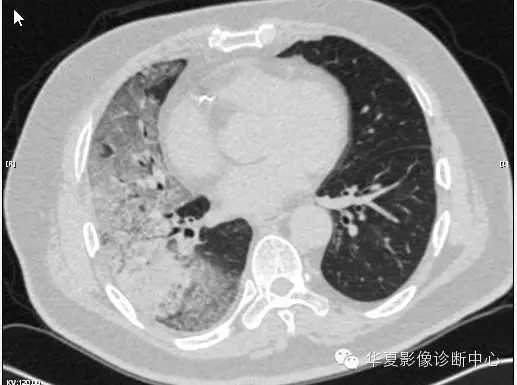

【病例学习】甲型H7N9禽流感一例

男性 63

发热咳嗽5天

2013-4-5拍片示右肺实变,收入院,追问病史,发病期间肌肉酸痛,头痛,无腹痛腹泻,无明显胸闷气急,无意识改变。有高血压病史,无其它病史。

2013-4-7CT进一步检查。

最终诊断:H7N9。